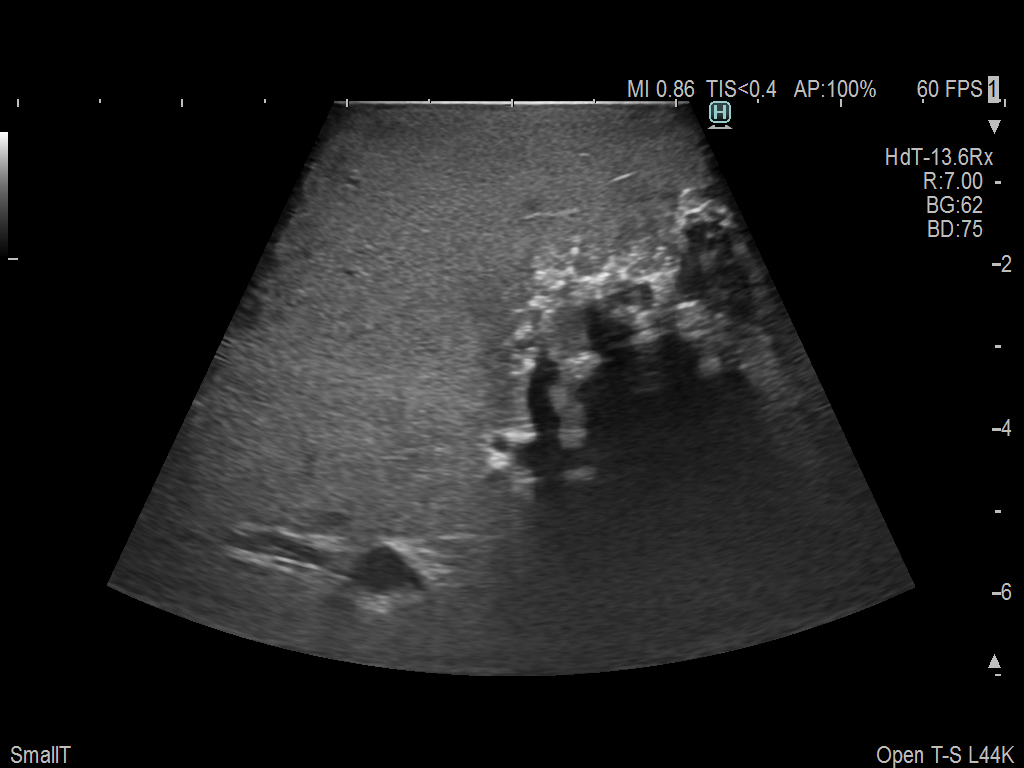

Exclusive 10mm side-fire linear array transducer with 2.87mm diameter is ideal for real-time visualization through and behind structures and instant, scalable definition of anatomy and vascularity including the ability to delineate and define tumor margins.